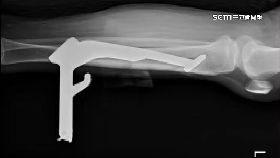

停車立中柱「刺穿小腿」 23公分直達膝蓋

高雄一名女機車騎士停車用左腳立中柱時,中柱居然整根刺...